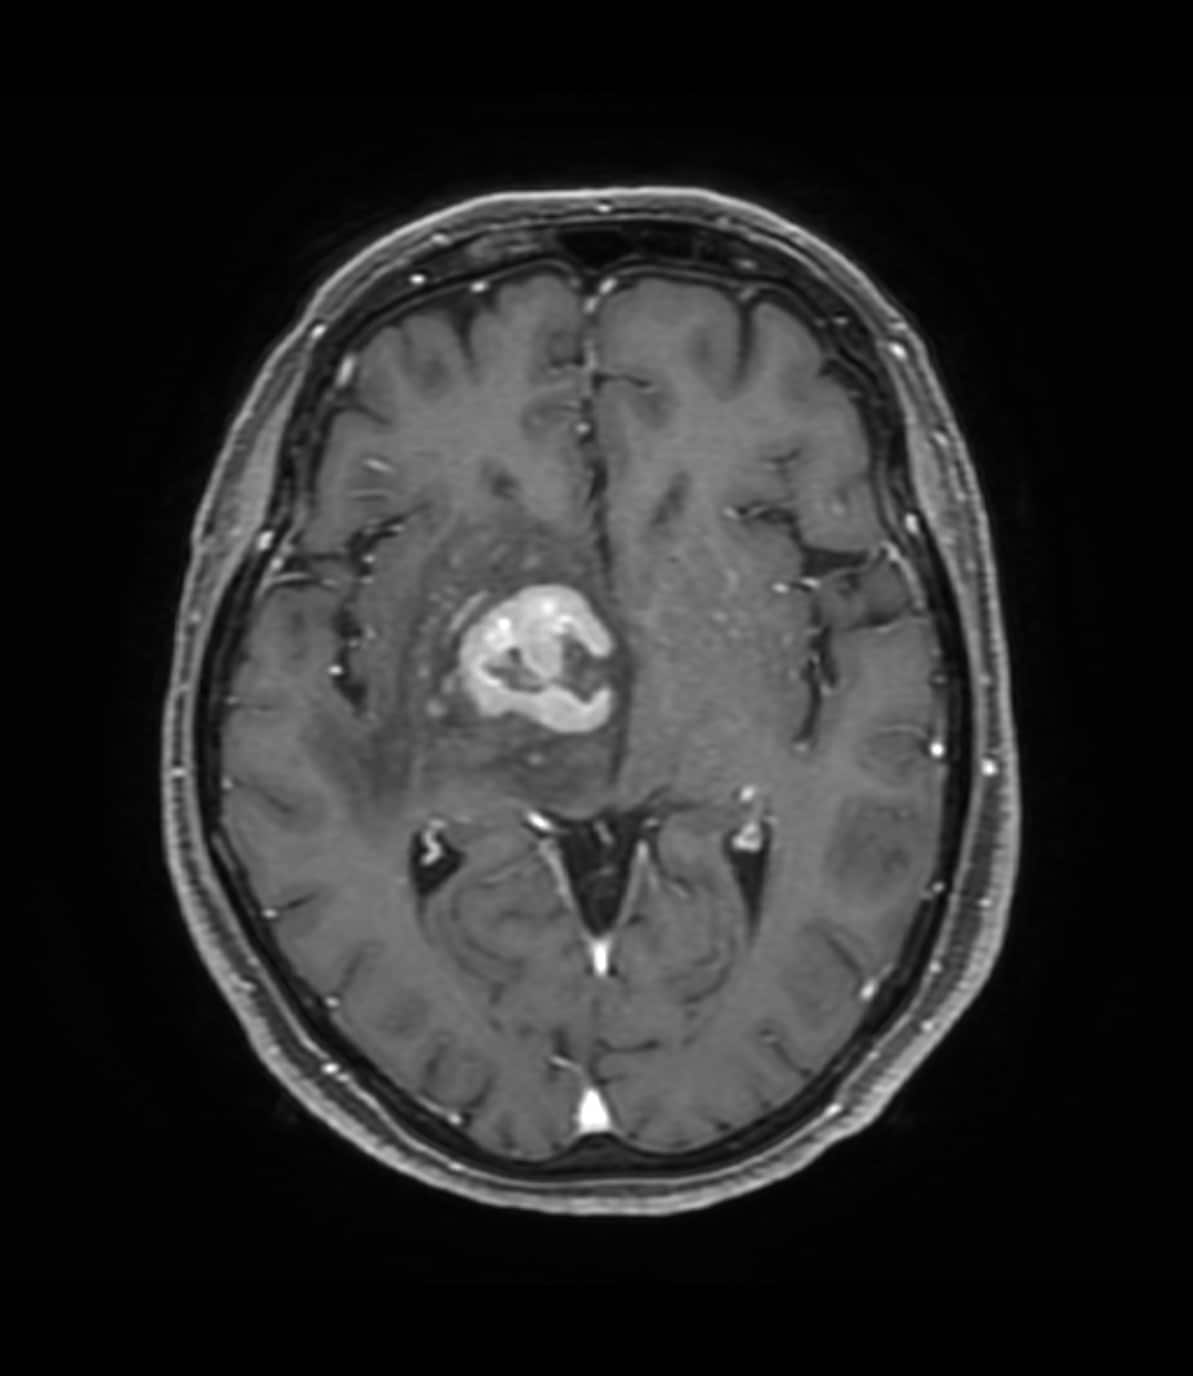

70歳代、女性、57kg、中枢神経原発悪性リンパ腫(PCNSL)

1ヶ月前から左不全麻痺、右眼瞼下垂、左同名半盲を認めた患者。近医脳外科でMRI施行し脳腫瘍を指摘されたため、当院に紹介となった。生検前の精査目的で造影MRI施行となった。

右基底核~視床~右中脳腹側にかけて均一で強いリング状増強効果を呈する腫瘤を認める。周囲に浮腫と思われるFLAIR 高信号域を認める。主病変の濃染部分はFLAIR等信号、DWI 高信号、ADCmap 低信号を呈している。MRS(TE=144)でChoが上昇、CrとNAAが低下している。ASLでは血流の顕著な上昇は認めない。中枢神経原発悪性リンパ腫(PCNSL)が疑われた。脳腫瘍生検の結果、中枢神経原発悪性リンパ腫(PCNSL)と診断された。

当該疾患の診断における造影MRIの役割

造影MRIにより腫瘍の範囲を正確に確認でき、腫瘍生検を行う際に病変を的確に捉えることができるようになると思われる。本症例のように浮腫を伴う脳腫瘍の場合、単純MRIのみでは浮腫と腫瘍の境界が不明瞭であり、腫瘍の範囲を把握するために造影MRIが必要と思われる。